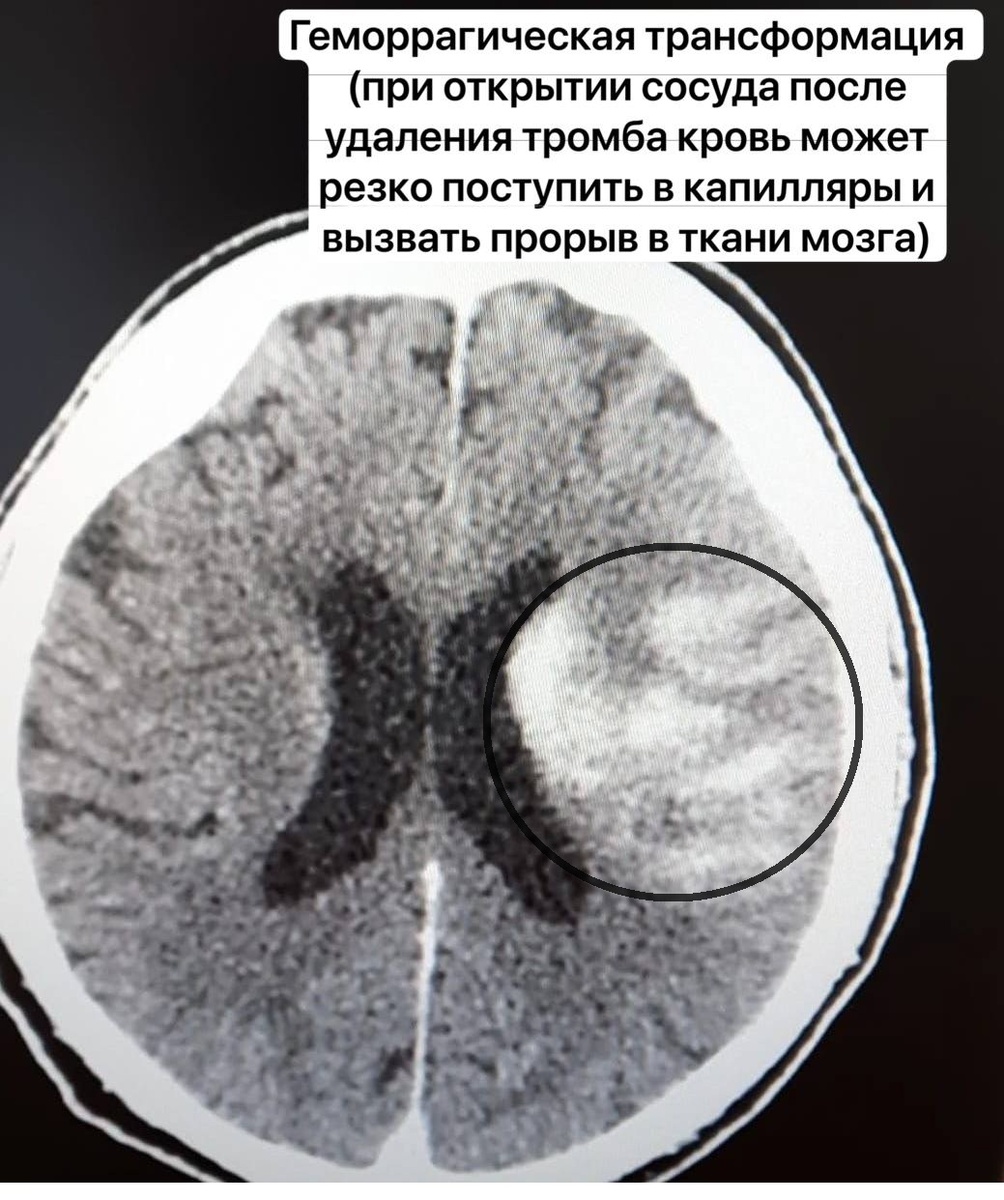

Сначала невролог провела процедуру по расцеплению тромба в сосуде, затем пациента направили в отделение рентгенохирургических методов диагностики и лечения. Там была проведена операция по вакуумному отсасыванию тромба.

«В итоге операция по удалению тромба из средней трети левой внутренней сонной артерии была успешно проведена. Уже на операционном столе пациент мог отвечать на вопросы и двигать рукой», – рассказывают в региональном министерстве здравоохранения.